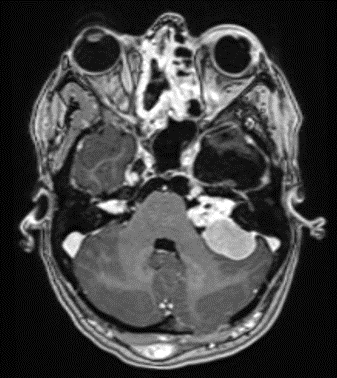

Hintergrund Genetik und klinische Ausprägung Neurofibromatose Typ 2 (NF2) ist eine autosomal-dominat vererbte Erkrankung, die durch multiple Tumoren des zentralen und peripheren Nervensystems sowie Läsionen der Augen und der Haut charakterisiert ist (1;2). Die Prävalenz liegt bei 1:60.000, die Inzidenz bei etwa 1:33.000 (1:25.000 bis 1:87.000) Geburten (3-6). Das betroffene Gen auf dem Chromosom 22q12 wurde 1993 von Arbeitsgruppen in Quebec und Boston identifiziert (7;8). Es kodiert ein Tumorsupressorprotein, welches als MERLIN (Moesin-Ezrin-Radixin-Like-Protein) oder Schwannomin bezeichnet wird. Patienten erben entweder eine Keimzellmutation des Allels eines Elternteils oder erkranken durch eine postzygotische Neumutation eines Allels während der Embryogenese. Molekulargenetische Tests werden bestenfalls an frisch entnommenem Tumorgewebe bei der Entfernung des ersten Tumors durchgeführt (9;10). Das ubiquitäre Vorkommen von MERLIN in nahezu allen Zelltypen des Menschen erklärt die vielgestaltige Symptomatik im Falle einer systemischen Mutation (Keimbahnmutation). Am häufigsten entwickeln sich bilaterale Vestibularisschwannome (VS, Abb. 1). Intrakranielle Meningeome und Tumore im Wirbelkanal und Rückenmark sind ebenfalls häufig, ebenso wie Schwannome der peripheren Nerven und anderer Hirnnerven. Entgegen der Benennung der Erkrankungen treten dabei Neurofibrome – Tumore der Nervenfasern – sehr selten auf. Vorherrschend sind Schwannome (Synonym: Neurinome), also Tumore der Nervenscheiden (Schwann-Zellen). Persistierende Reparaturvorgänge durch Schwann-Zellen in einem veränderten axonalen Mikromilieu tragen wahrscheinlich zur Schwannomentstehung bei (11).